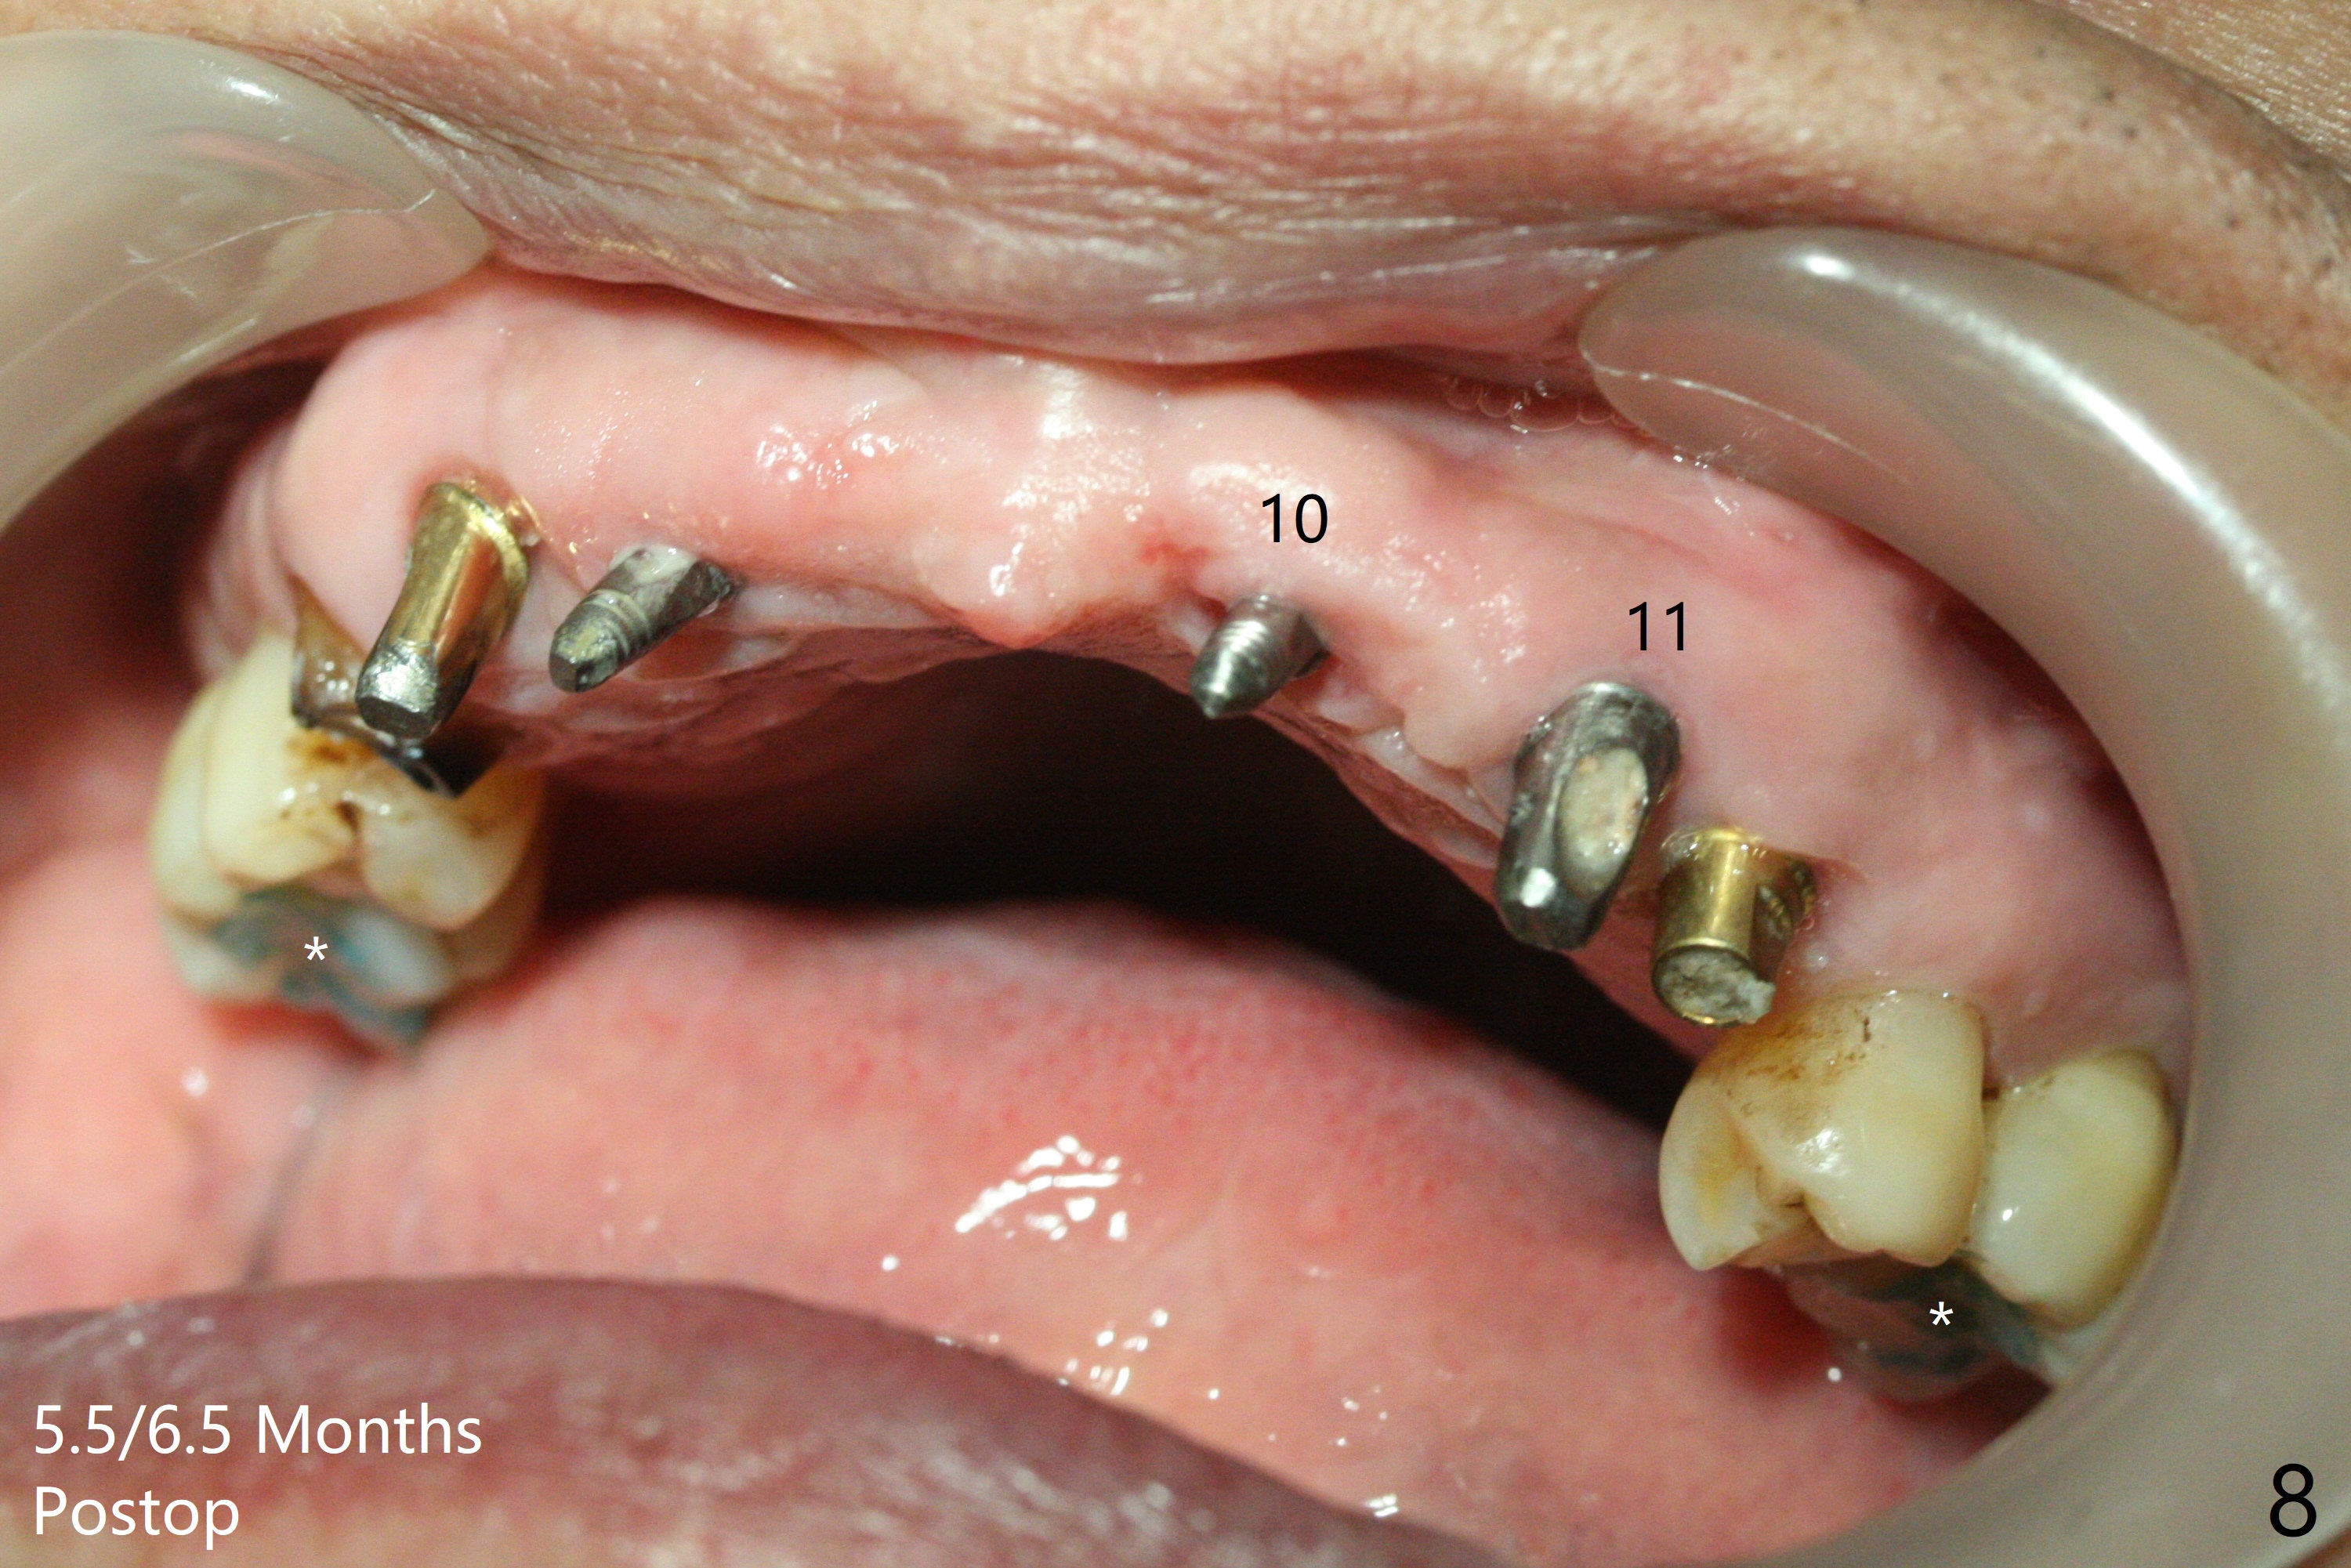

To have enough clearance for the splinted provisional at #6-12 (Fig.1 *), composite has been placed in the posterior teeth (bilateral, *, Fig.2). When the composite is removed, there is no clearance between the implants/abutments of #7 or 10 (Fig.3). Incision is made with removal of the 1-piece implant at #7; there is enough bone to move the osteotomy buccal (Fig.4 arrowhead). When the same implant is placed buccal (Fig.5), there is sufficient clearance for restoration (Fig.6 *), while there is still enough buccal bone left (Fig.7). When the patient returns 5.5 (for #7 and 10)/6.5 (#6,11,12) months postop, his chief complaint is tenderness lingual to #11. In fact, the abutment screw is loose at #11, while the implant at #10 has mobility (Fig.8), which is related to loss of the posterior stops (*) due to wear. There is slight bone loss mesial to #10 implant 5.5 months postop (Fig.10, as compared Fig.9). CBCT taken 5.5/6.5 months postop shows no bone loss (Fig.11-15). The 3x14 mm 1-piece implant at #10 is mobile 9 months postop and is removed and replaced by a 3.5x13 mm 2-piece one with slightly buccal osteotomy (Fig.16). PAs are taken prior to impression (Fig.17,18). The abutment at #12 is loose (<). More composite needs to be added to the occlusal surface of the upper posterior teeth. Finally the patient agrees to have crowns for the upper posterior teeth.